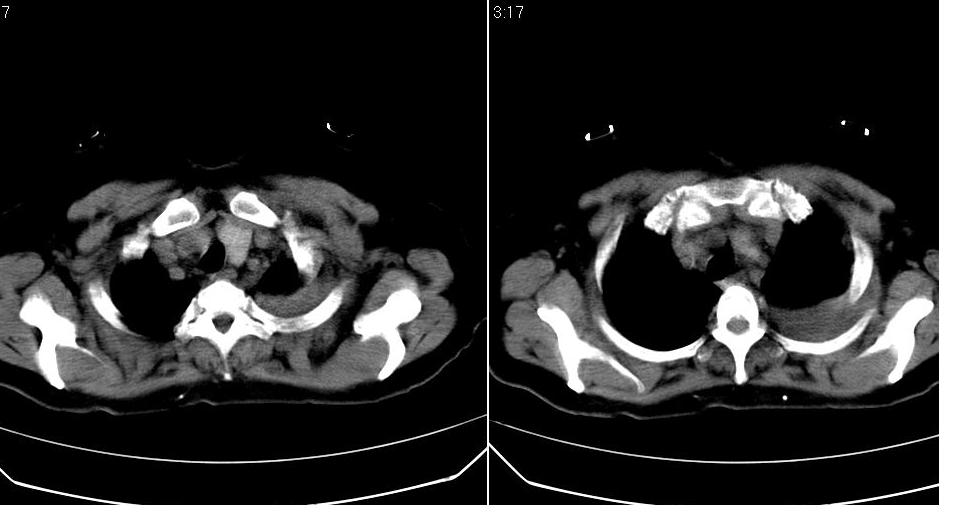

女 59岁,胸背疼,不咳嗽,不咳痰,不发热。

左肺下叶中心性肺癌?tb?;并气胸

1)考虑左肺下叶背段周围型肺癌并左肺下叶及左侧胸膜转移。2)左侧胸腔积液。3)左冠状动脉钙化。